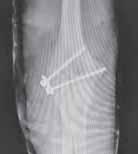

Rycina 17.81.

A, B – Genu recurvatum u pacjenta po złamaniu okolicy proksymalnej części chrząstki nasadowej piszczeli.

Rycina 17.82.

Uszkodzenie tętnicy podkolanowej wskutek złuszczenia nasady bliższej kości piszczelowej (S-H 1). Zagrożenie rozwojem zespołu przedziałów powięziowych jest poważne.